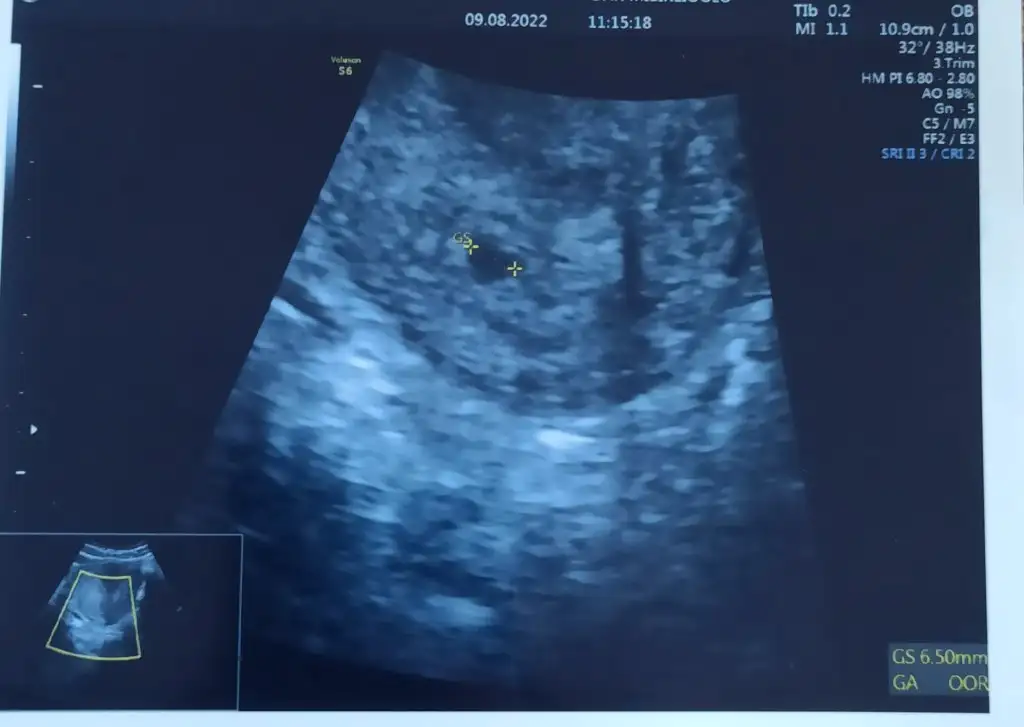

böyle güm güm bi ses duydun mu canım ben duyamadım çünkü kalbi pıt pıt hareket ediyodu onu gördüm ama net olarakKizlar bende kalp atışını duydum hamdolsun, 6+1 iz bugün, bebek 5 mm dedi, bir sıkıntı yok hamdolsun

Dün benimki de 4 mmdiDün akşam benim hesabıma göre 6+2 , doktorun hesabına göre 6+0 da bebegi ve kalp atısını gördük kızlar :)

benim bebek de 4 mm miş bu arada

Bugün benimki de 5 mm olmuştur 6+2 de bendenKizlar bende kalp atışını duydum hamdolsun, 6+1 iz bugün, bebek 5 mm dedi, bir sıkıntı yok hamdolsun